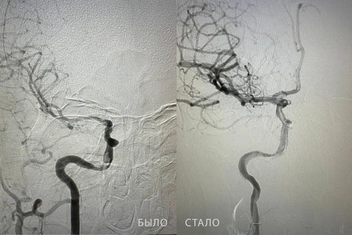

Извлекли гигантский тромб

Однажды в ОКБ № 3 привезли очень тяжелого пациента: мужчина терял сознание, речь была нарушена, лицо перекошено, а левая часть тела парализована. Очевидно, это был инсульт.

Врачи нашли у него тромб в сонной артерии. Невролог Жахонбек Латипов и ангиохирург Бакназар Абдыкадыров провели сложнейшую операцию продолжительностью более получаса, чтобы спасти тюменца.

— Вовремя вызванная скорая помощь и четкая командная работа специалистов — ключ к успешному исходу при инсульте. В данном случае каждая минута была на счету, и нам удалось вернуть пациента к полноценной жизни, — рассказал доктор Латипов.

Из артерии хирург извлек тромб размером почти 2 см. Кровоток удалось восстановить. А благодаря реабилитации мужчина восстановил речь, симметрию лица и подвижной левой части тела.